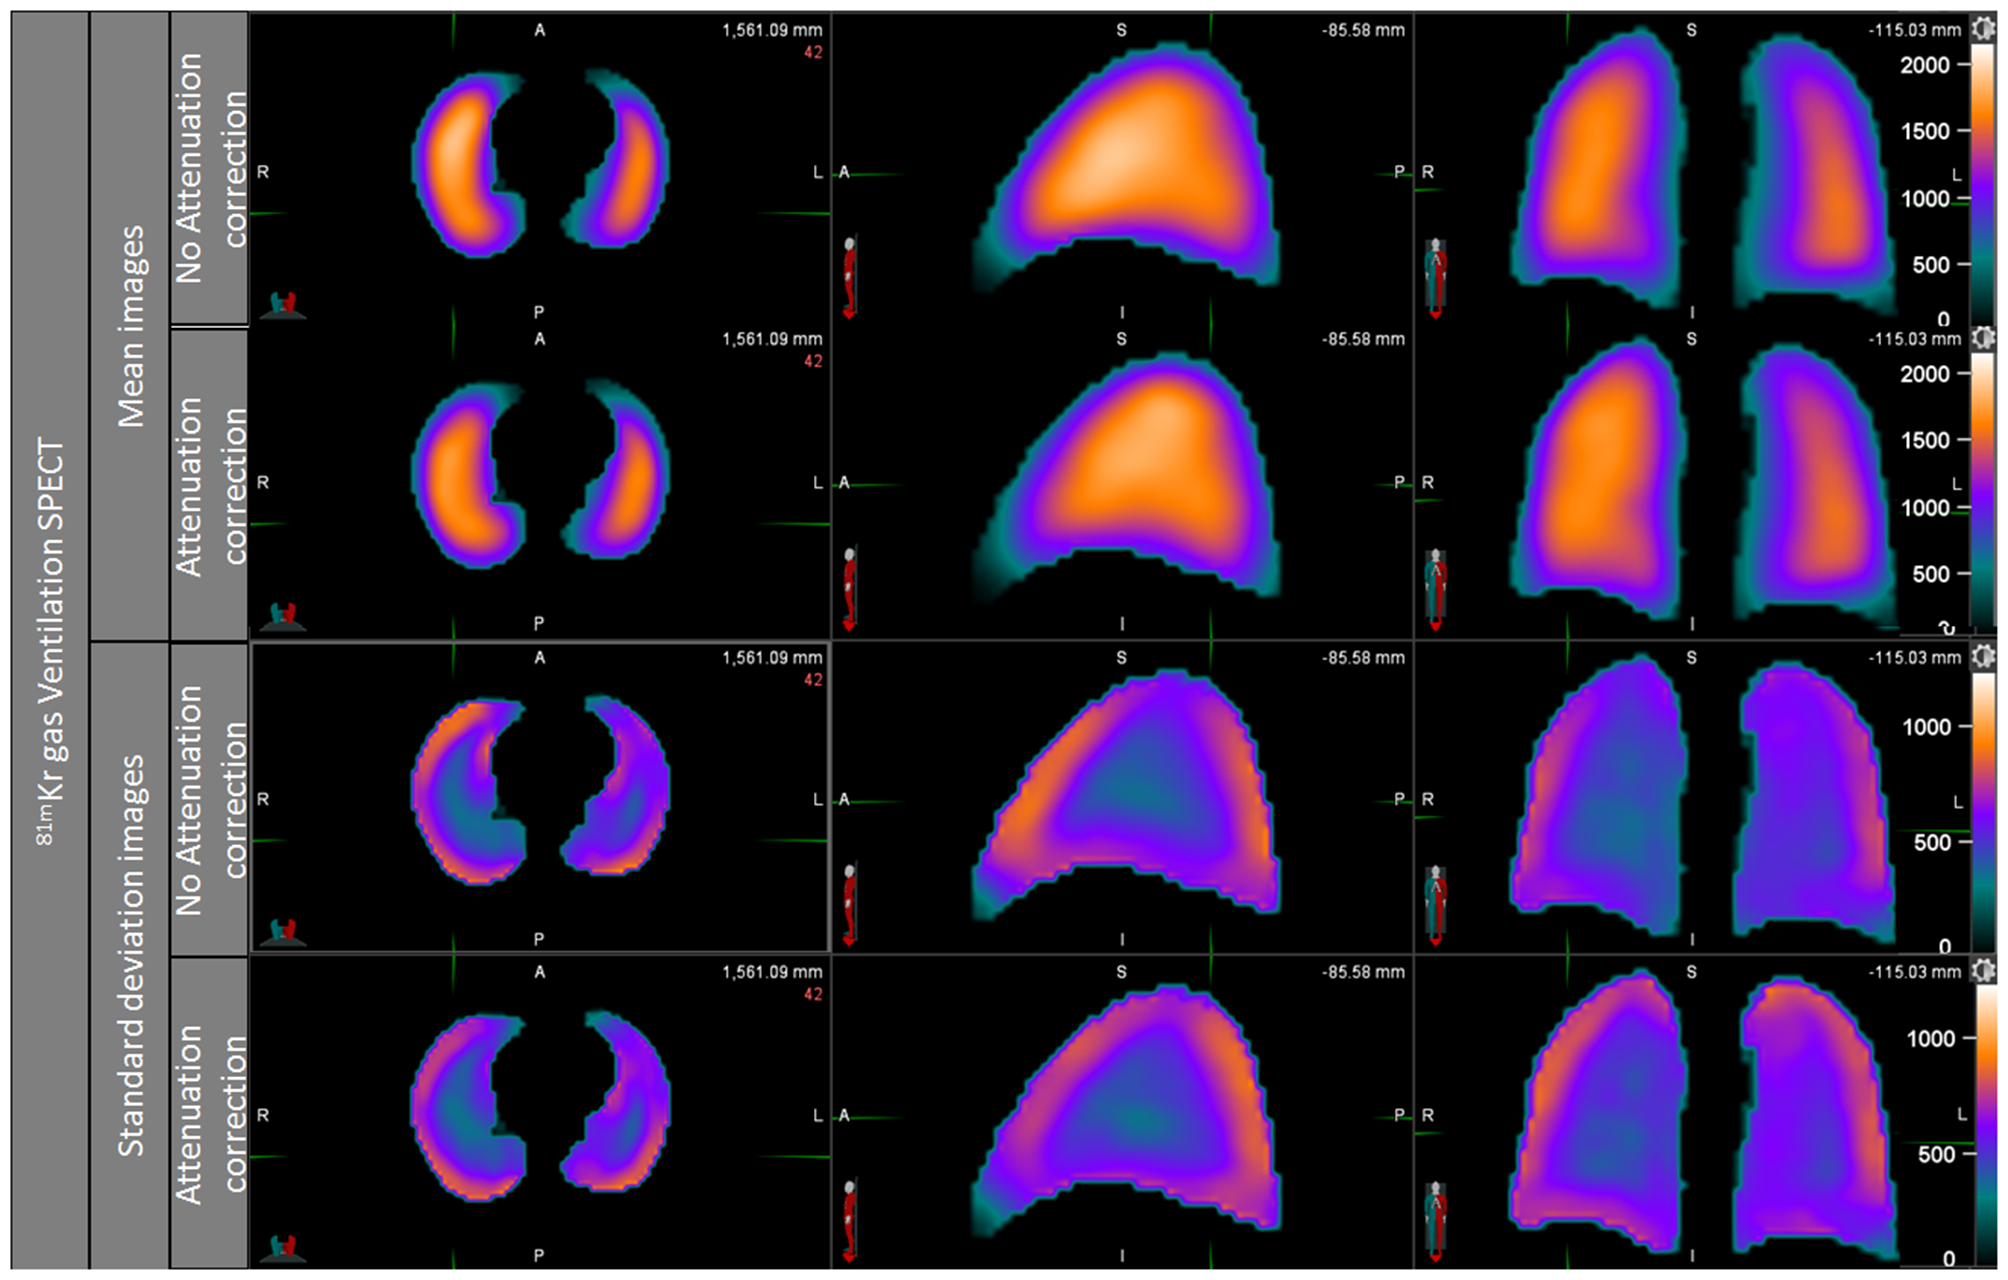

The ventilation mean map showed a slightly positive posterior to anterior gradient on NoAC mean ventilation map, while the visual observation of AC ventilation mean map showed no gradient (Figure 3). The NoAC ventilation SD map showed a higher variability in the periphery of the lungs. The higher variability was found in the anterior area of the noAC map.

Figure 3

Ventilation mean map and standard deviation map, noAC, and AC.